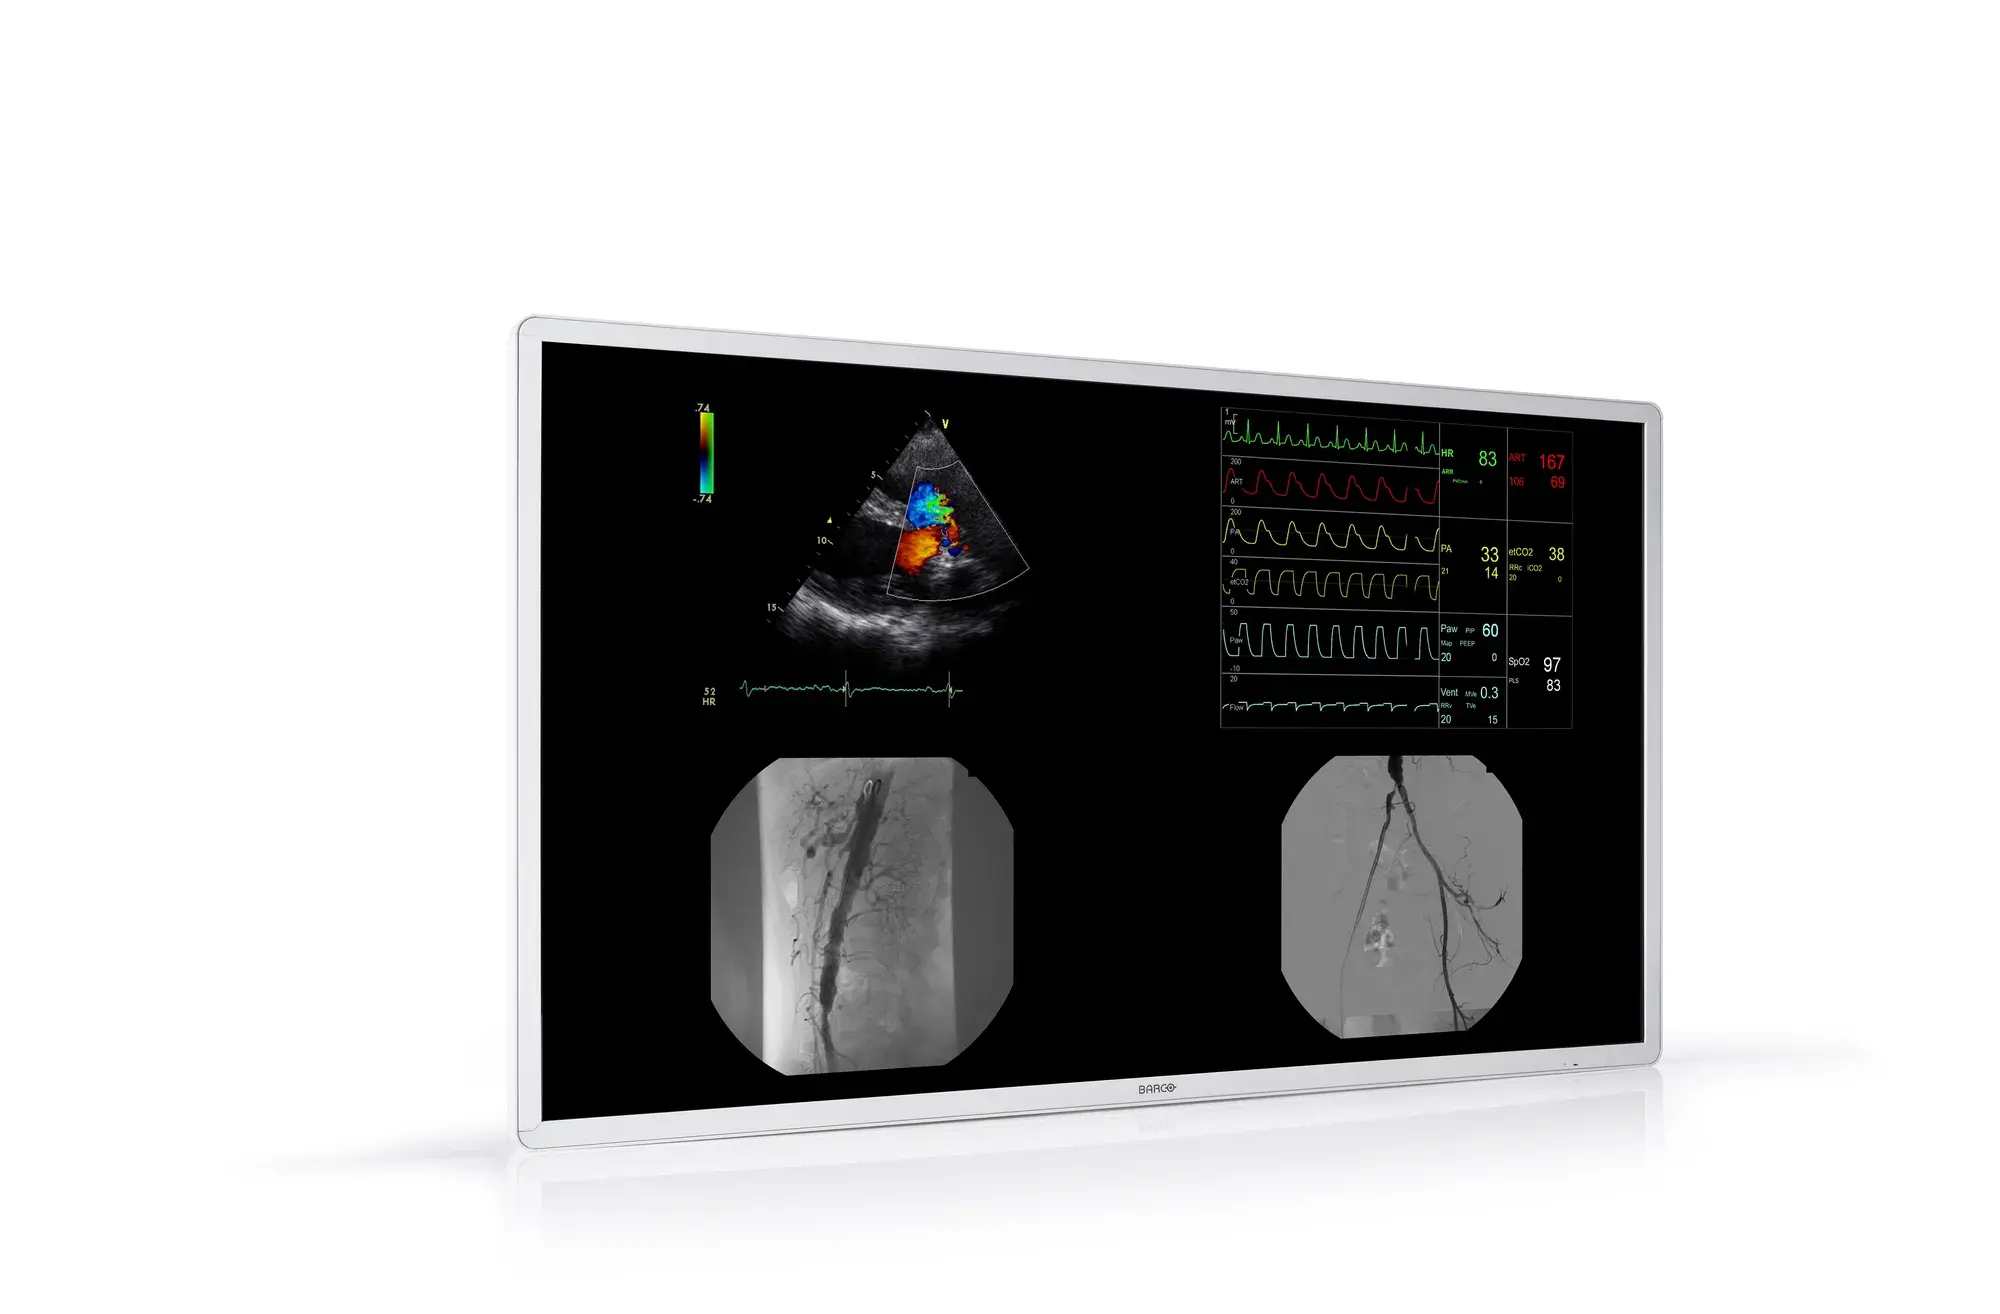

MDAC-8355 yra medicininio ekrano modelis, dažnai naudojamas diagnostikos tikslais, ypač medicinos įstaigose, tokiose kaip ligoninės, klinikos ar diagnostikos centrai. Šie ekranai yra skirti tiksliai ir aiškiai rodyti medicininius vaizdus, tokius kaip rentgeno nuotraukos, CT skenavimai ir ultragarso vaizdai, ir atitinka aukščiausius standartus, užtikrinančius kokybę bei saugumą.

MDAC-8355 yra 55 colių 4K itin didelės raiškos medicininės klasės ITE ekranas, sukurtas išskirtinai originalios įrangos gamintojams (OEM) ir sistemų integratoriams, dirbantiems vaizdo valdomos terapijos srityje.

Dėl unikalios integruotos vidinės vaizdo kompozicijos galimybės MDAC-8355 tinka rodyti daugiamodalinius vaizdus iš platesnio spektro vaizdo valdomų sistemų.

MDAC-8355 galima integruoti į jūsų vaizdo valdomą sistemą, kad būtų galima padėti klinikinėms komandoms (intervencinės radiologijos, kardiologijos, radiacinės onkologijos, artimosios infraraudonosios spinduliuotės valdomos chirurgijos ir endovaskulinės robotikos srityse), atliekančioms tiek įprastas, tiek sudėtingas procedūras, kai vienu metu reikia rodyti aukštos kokybės, švarius, ryškius ir aiškesnius daugiamodalinius vaizdus. Jį galima tvirtinti prie sienos arba lubų, o specifinėms klinikinėms reikmėms supakuoti ant medicininio vežimėlio.

Užtikrinus viso naudojimo laiko šviesumo stabilumą ir DICOM kalibravimą, klinikinės komandos, kurios greitai priima sprendimus vaizdo valdomų procedūrų metu, gali dirbti optimaliai.